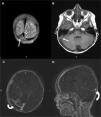

Patient 1A 15-year-old boy was admitted to our clinic with edema and 10kg weight gain in a month. Physical examination (PE) showed generalized edema and ascites. Urinary examination showed 246mg/m2/h proteinuria. Serum albumin level was 0.8g/dl, cholesterol and triglyceride levels were 375mg/dl and 190mg/dl respectively. Hemoglobin (Hb) level was 16.2g/dl. Renal biopsy was compatible with MCD. He was put on 60mg/day prednisone treatment and remission was achieved on the 22nd day. Steroid was used as 60mg/day for a month and tapered over 3 months. The day after cessation of prednisone generalized edema, headache and vomiting started. Laboratory investigations showed severe proteinuria, 1060mg/m2/h and a serum albumin of 0.8g/dl. His Hb level was 21.6g/dl and hematocrit (htc) 63.8%. He was put back on 60mg/day prednisone and intravenous fluid, albumin replacement, acetylsalicylic acid therapy were started. Cranial computed tomography (CT) was normal. Next day PE revealed lateral gaze palsy of the right eye. Cranial magnetic resonance imaging (MRI) and MR venography (MRV) were performed which showed subacute superior sagittal, right sigmoid and transverse sinus thromboses (Fig. 1A and B). Immediate anticoagulation with heparin was started. Investigations for inherited thrombotic risk factors were negative. On the third day of admission lateral gaze became normal. Two weeks later a repeat MRV showed partial recanalization of the thrombi (Fig. 1C and D). Remission of NS was achieved on the 35th day of steroid treatment, then the dose was decreased and the patient was put on cyclosporine. He had complete neurological recovery and did not experience recurrence of NS or thrombosis during the two-year follow-up.

Coronal T2-weighted (A) and transverse T1-weighted (B) MR images show hyperintense thrombus in transverse and sigmoid sinuses (arrows). Contrast-enhanced MR angiography axial (C) and sagittal (D) reformatted images demonstrate thrombus as hypointense filling defects in right transverse sinus (curved-arrows).